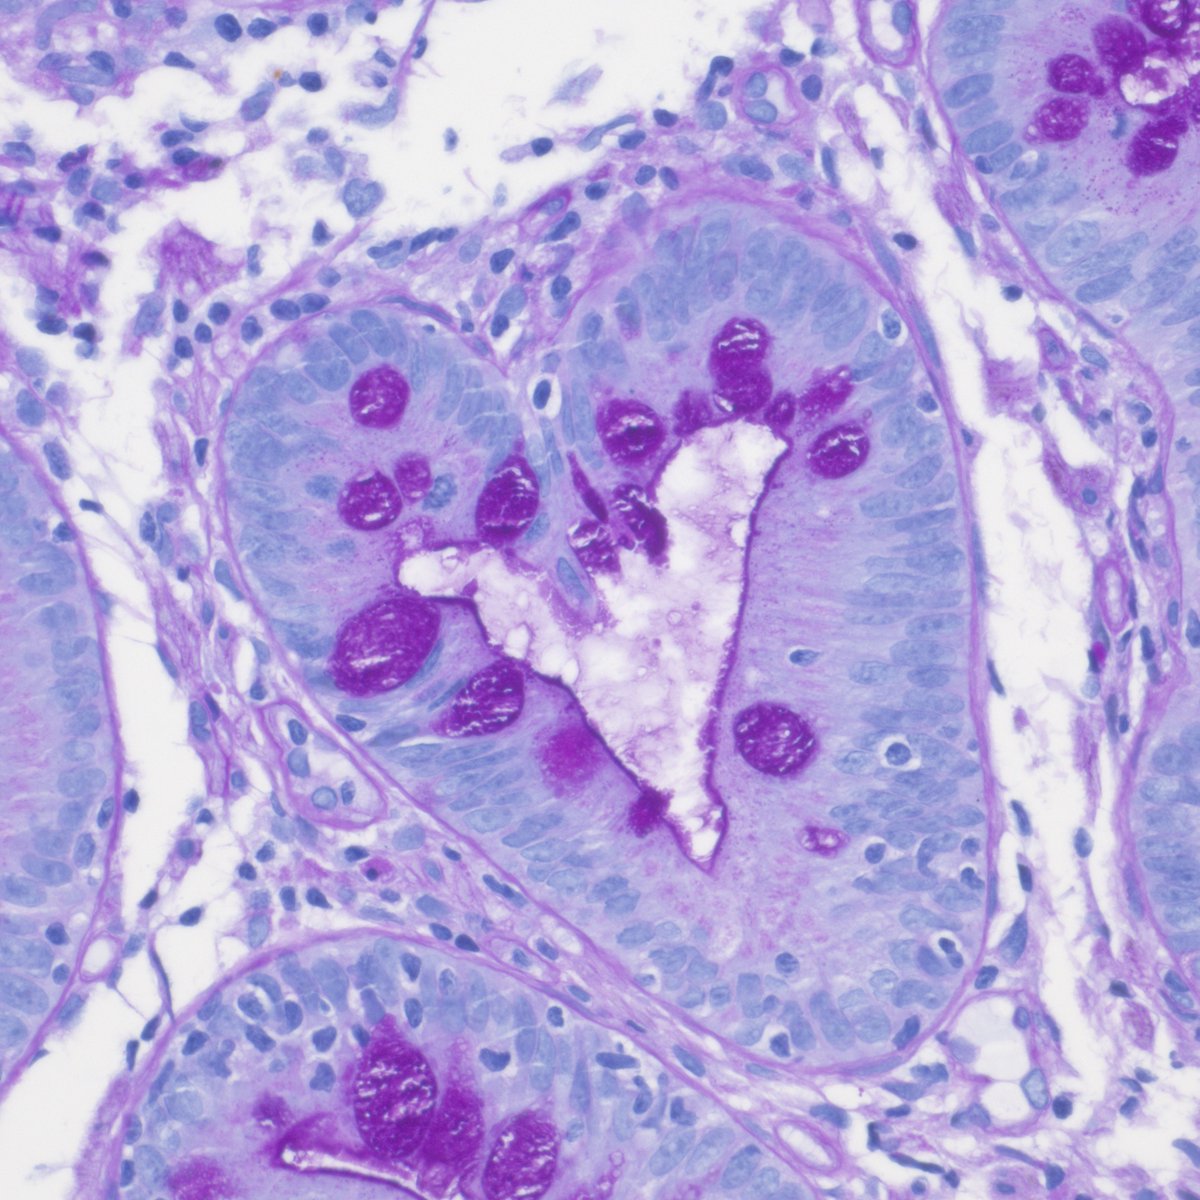

jejunal biopsy; marked villous atrophy, IEL increase, crypt hyperplasia, absent plasma cells in LP- your Dg?

❤️❤️#gipath